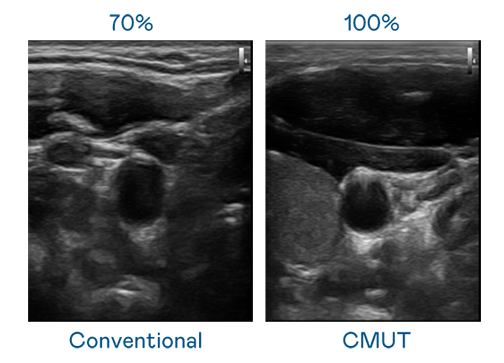

CMUT 技术是一种用电容式微机电元件来产生超音波讯号的技术。与传统 PZT 压电式技术相比,CMUT 频宽增加 30%,更宽频的超音波讯号让影像解析度大幅提升,是实现高影像品质医疗超音波扫描、促进精准医疗发展的关键技术。

超音波影像的解析度高低,首先取决于探头能发出的讯号频宽。ibet CMUT 可提供高清晰的超音波讯号,提供高频宽、高灵敏度、影像纹理细节更高的超音波影像,协助医护人员缩短影像判读时间及利用精准的医疗影像进行诊断。